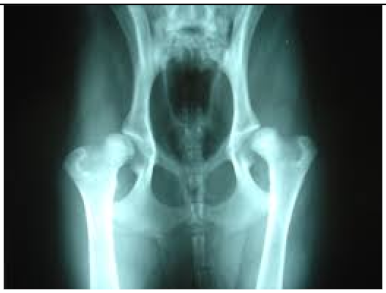

2.6.1. Test Procedure

The stress test involved simulating varying numbers of concurrent users querying the system. For each LLM, we executed 20 clinically relevant prompts, as shown in (Table A2) in the Appendix A. For each VLM, 10 different images with 2 prompts per image resulting in a total of 20 prompts per model were tested. The specific prompts used are listed in (Table A3) in the Appendix A. We tested user loads of 10, 20, 30, 40, 50, 75, 100, 125, and 150 users. In order to measure the robustness of the container as well as the robustness of JAVIS, this experiment queried the JAVIS back-end to measure the complete roundtrip response times. This approach ensured that the test accurately reflected real-world usage scenarios, including the overhead of back-end processing and model orchestration.

JAVIS supports multimodal LLMs or VLMs, allowing the integration of various image types (JPG, PNG, etc.). This enhancement significantly increases the system’s versatility in handling diverse clinical inputs, enabling more comprehensive and accurate patient interactions.